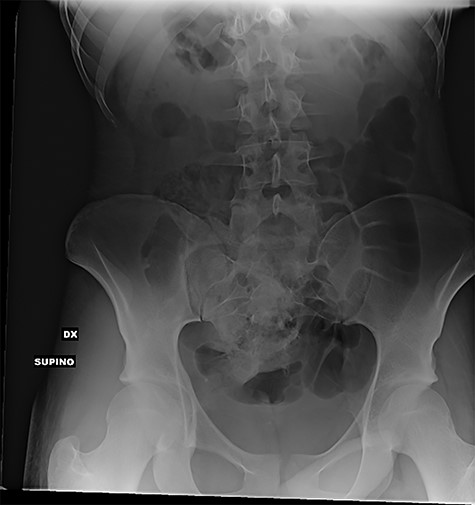

At hospitalization, the clinical examination revealed moderate pain in the lower left part of the abdomen. Laboratory analyses demonstrated moderate neutrophilic leukocytosis. Abdominal X-rays revealed the presence of many radiopaque foreign bodies on the projection of the rectum, referable to stylus batteries (Figs 1 and 2).

Erect abdominal X-rays (frontal view): presence of many radiopaque foreign bodies in the pelvis